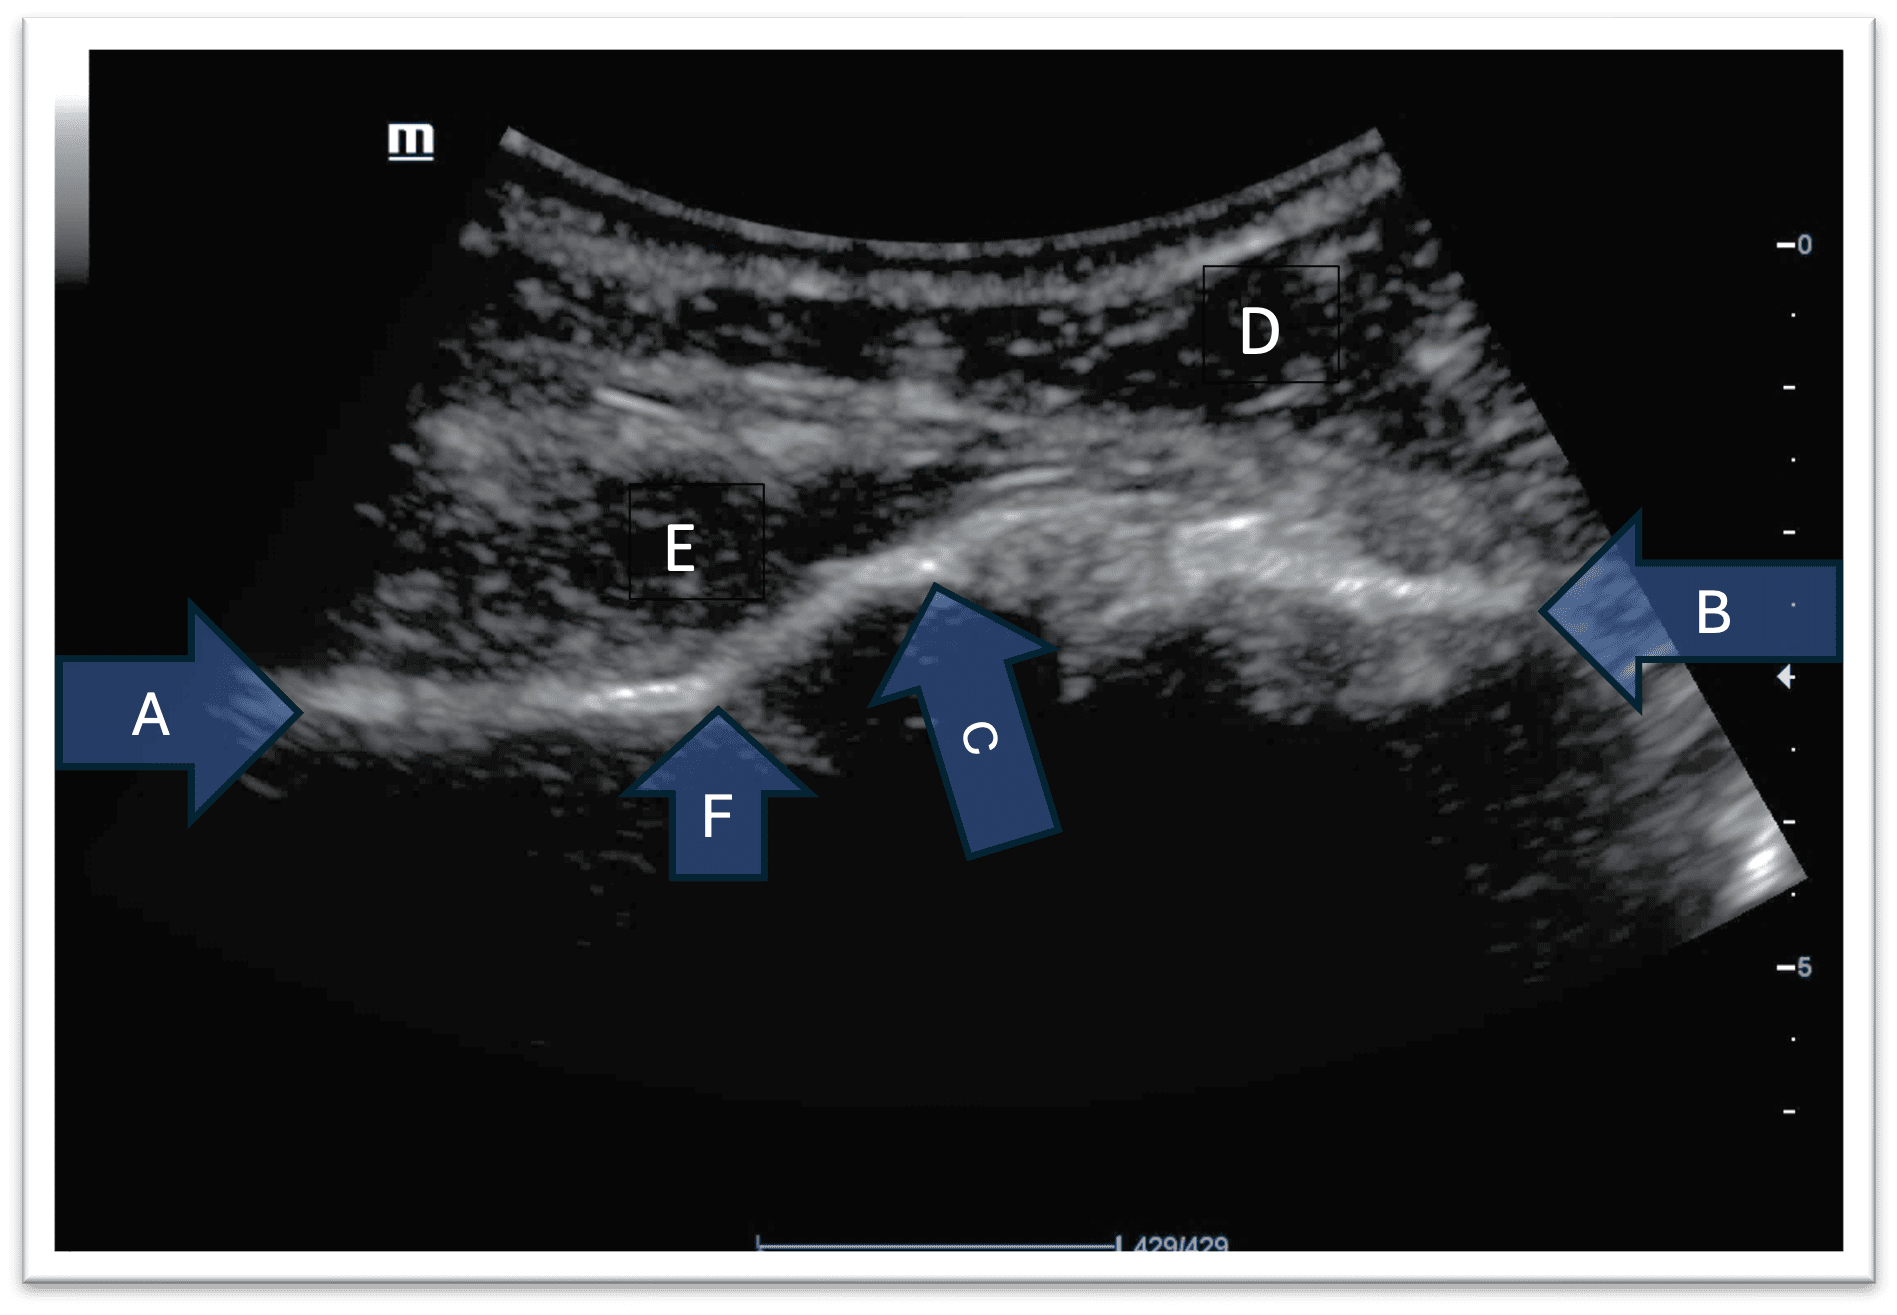

Name structures A, B, C, D, E on the image given below.

Figure 1. Ultrasound scan image of a normal right shoulder joint (posteriorly) The image left to right corresponds to the patient’s medial to lateral.

Answer

A – Body of scapula

B – Head of humerus

C – Glenoid

D – Deltoid muscle

E – Infraspinatus muscle

F – Spinoglenoid notch